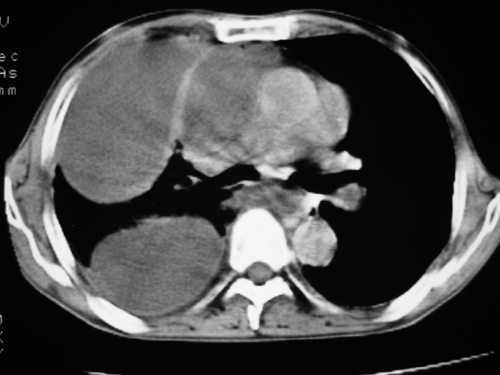

以下是引用yangyudong333在2008-4-29 5:46:00的发言:[br]1左上叶结节呈分叶状,边缘毛刺,考虑肺癌并纵隔淋巴结转移可能性大,结核待排,[br] [br]2右侧多发包裹性胸腔积液

以下是引用zsl6918在2008-4-29 9:15:00的发言:[br]右侧包裹性积液穿刺术后改变,肺内多发结节不除外转移可能。建议查胸水,问病史。